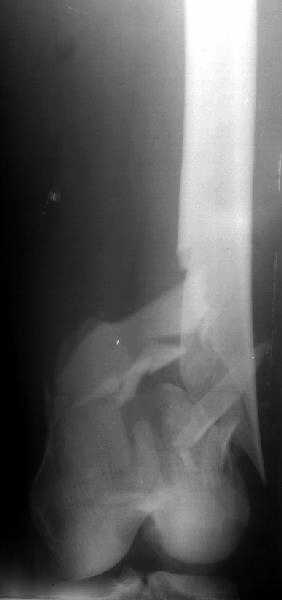

DMI> Hope it didn`t have intra articular extension. If u had encountered this

The discussed case was pure metaphyseal, not T- or Y- intraarticular.

Though the second case was C2 fracture, and it took to perform closed reduction with joystick wires, and then insert opposite olive wires.

DMI> Please enlighten about your technique, positioning of pt. ,Type of table,

A small wire distractor was used for intra op reduction. Position - supine with adduction and internal rotation of the affected limb.